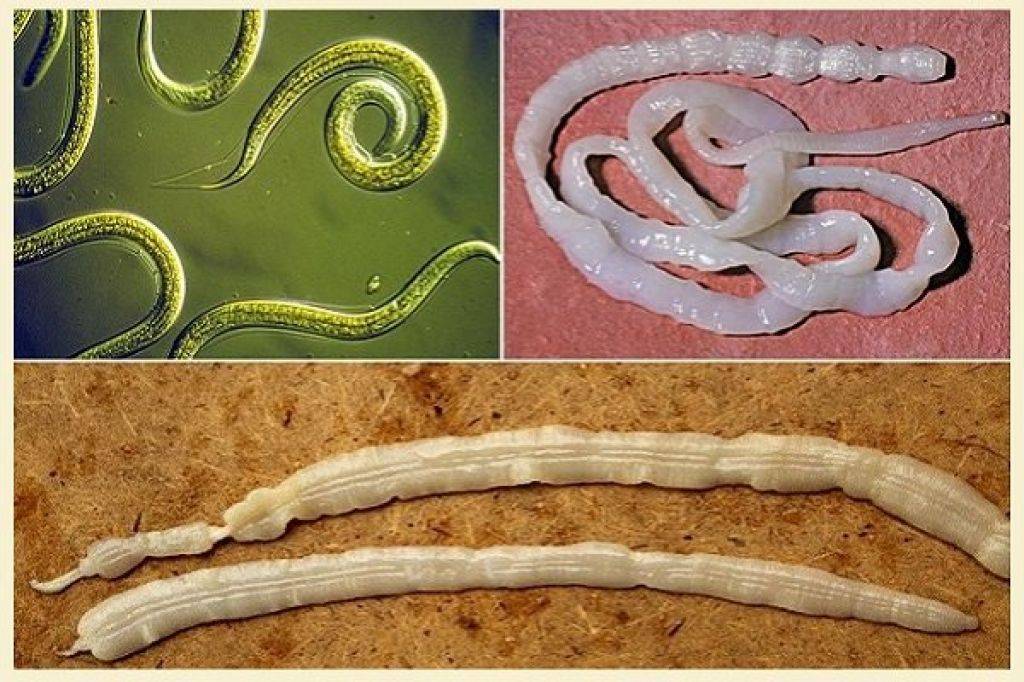

Фотографии нематод, цестод и трематод в природе

Раздел: Другие животные